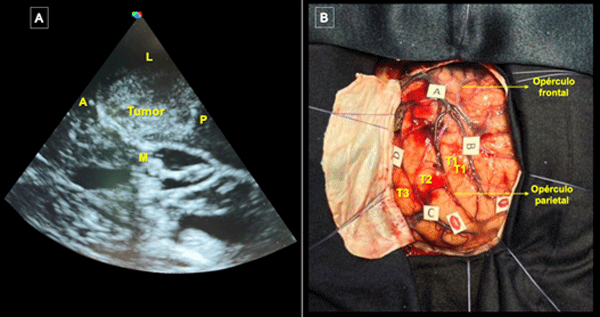

Se efectuó corticotomía trans-T2 y disección microquirúrgica hasta exponer una lesión intraaxial de aspecto hipervascularizada y duroelástica. Durante la disección circunferencial con preservación del plano pial la paciente realizó multitareas y se estimuló continuamente la zona subcortical para definir los límites funcionales: a nivel anterior parafasia fonológica (fascículo arcuato) y a nivel posterior alexia (fascículo longitudinal inferior). Durante la resección se observó la exteriorización espontánea de material purulento contenido en el tumor (Figura 5 A). Se logró una resección completa corroborándose el atrio ventricular como límite medial (Figura 5 B, C y D). Se procuró una hemostasia minuciosa del lecho quirúrgico y una vez finalizada se hizo un control ecográfico sin evidencia de remanente tumoral. La paciente toleró adecuadamente el procedimiento quirúrgico e ingresó despierta a la unidad de cuidados intensivos.

Figura 5. Visión microscópica. A) Visión microscópica de exteriorización espontánea de material purulento contenido en el tumor. B) Visión microscópica de la lesión siendo retirada del lecho quirúrgico. C) Lecho quirúrgico tapizado con material hemostático. D) Resección completa del tumor.